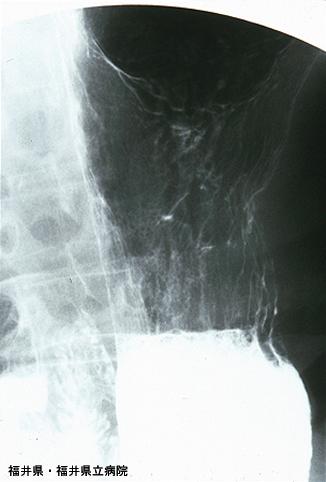

Posted by: Fukui Pref., 福井県立病院 (Dr.細川)

Criteria of Hist.ClassificationMalignant epithelial tumor/Signet-ring cellcarcinoma

LocationStomach/Body

Technique, MethodX-ray

Macroscopic TypesType 3 Ulcerated type with infiltration/

Size10 - 14

Depth of Tumor Invasionmuscularis propria